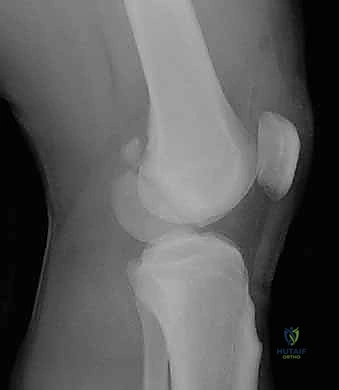

- الأشعة السينية (X-Rays): أخذ صور من زوايا متعددة (أمامي خلفي، وجانبي) لتحديد موقع الكسر ونوعه.

المرحلة الرابعة: التثبيت النهائي بالشرائح والمسامير (Fixation)

يتم استخدام "شرائح الإغلاق التشريحية" (Anatomical Locking Plates) المصنوعة من التيتانيوم عالي الجودة. هذه الشرائح مصممة خصيصاً لتأخذ شكل الجزء السفلي من عظم الفخذ. يتم تمرير الشريحة أسفل العضلات وتثبيتها بمسامير تغلق داخل الشريحة نفسها (Locking Screws)، مما يوفر ثباتاً ميكانيكياً هائلاً، حتى في حالات العظام الهشة.

في بعض الحالات المعقدة جداً، قد يتطلب الأمر استخدام شريحتين (Dual Plating) لضمان عدم تحرك الكسر أثناء فترة التعافي.